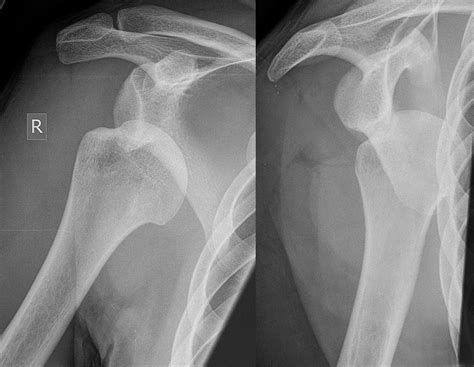

Diagnosis of Inferior Shoulder Dislocation

Diagnosing an inferior shoulder dislocation involves a combination of physical examination and imaging tests. The diagnostic process typically includes:

• Physical examination: A healthcare provider will assess the shoulder for deformity, swelling, and range of motion.

• X-rays: Imaging tests can confirm the dislocation and rule out fractures or other injuries.

• CT scan or MRI: These advanced imaging techniques may be used to evaluate the extent of the injury and plan treatment.

Accurate diagnosis is crucial for determining the appropriate course of treatment and ensuring a successful recovery.

• inferior shoulder dislocation xray

• inferior shoulder dislocation xr